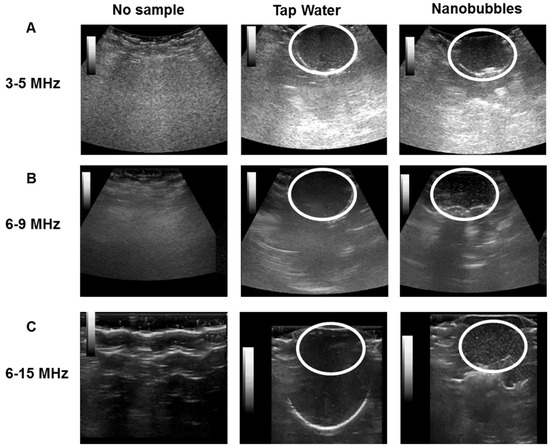

ONBs were inserted (dilution 1:10 in DPBS) in a balloon and compared with a tap water sample using a commercially available general electric (GE) ultrasound machine for three different transducers with frequencies of 3–5 MHz, 6–9 MHz and 6–15 MHz, respectively.

Figure 4 illustrates the ultrasonic imaged of ONBs. Figure 4A show ultrasonic images captured with a 3 to 5 MHz curved transducer. We captured the screens with no sample, tap water, and nanobubbles, respectively. There is no visible difference between the tap water and nanobubbles. Since most micro size bubbles have a resonance frequency in the range of 3 to 5 MHz, these results suggest that our sample did not include many microsize particles to exhibit higher contrast as compared to tap water. It also indicates that nanobubbles do not generate significant echoes compared with tap water. Figure 4B show images acquired with a 6 to 9 MHz linear probe. It can be observed that the contrast provided by nanobubbles is slightly improved compared with tap water. Figure 4C present images captured with a 6 to 15 MHz transducer. The difference between the nanobubbles and tap water is visible. Thus, we can confirm that nanobubbles generate echoes at higher frequencies, and they can be traced using commercial ultrasound equipment. The mechanical index (MI) during these images was kept constant at 0.15. White circles in the figures indicate the area of a balloon containing ONBs.

Ultrasonic imaging with commercial ultrasound machine revealed that these ONBs can be traced using ultrasound. Nanobubbles exhibited a higher contrast compared with tap water in ultrasound imaging at higher frequencies (6–15 MHz transducer), but this was not a very clear contrast difference, as is required for diagnostic applications. However, these bubbles can be traced using ultrasound, and, therefore, ultrasound can be employed for therapeutic purposes. At lower frequencies, in the range of 3 to 5 MHz, the contrast was not very significant compared with tap water. This is a further indication that our sample consisted of nano-sized particles and was generating a contrast at higher frequencies of ultrasound. This is more meaningful when nanobubbles are used for theranostic applications in combination with ultrasound.

Figure 4. Ultrasound images of ONBs. No sample, tap water, and nanobubbles were compared. (A) shows images with a 3 to 5 MHz transducer. (B) shows images for a 6 to 9 MHz transducer. (C) shows images with a 6 to 15 MHz transducer.